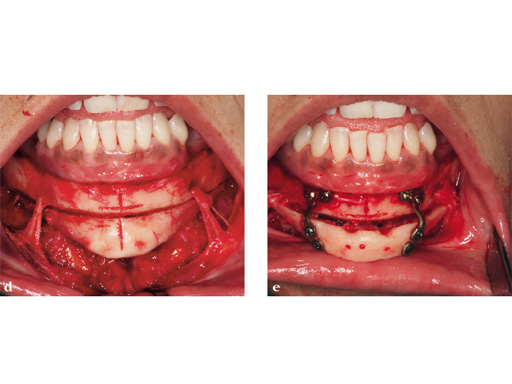

Case 2: Complex congenital deformity with distortion of alveolar processes and dentition, resulting in a 3.5 cm nonocclusion in the right maxillomandibular complex. Occlusion is exclusively controlled through the left second premolar to second molar. Piezosurgery was useful in this case due to complex anatomical deformities resulting in atypical positioning of the inferior alveolar canal on the right side. The cramped confines of dental and bony tissues in the deformed anatomy required an adequate type of osteotomy to do a significant yet controlled skeletal movement to overcome the vertical discrepancy intraorally, without changing the outer projection of the mandibular frame.

Case provided by Nils-Claudius Gellrich, Hannover, Germany